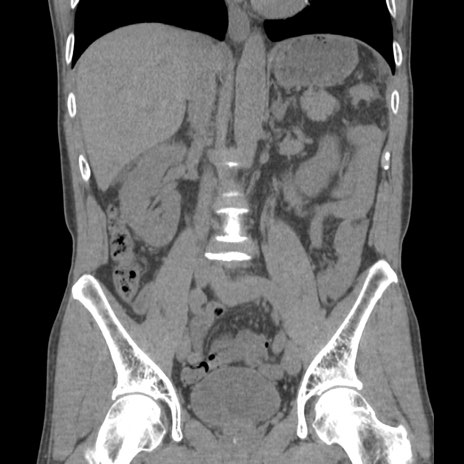

症例56 CT(冠状断像)

横断像